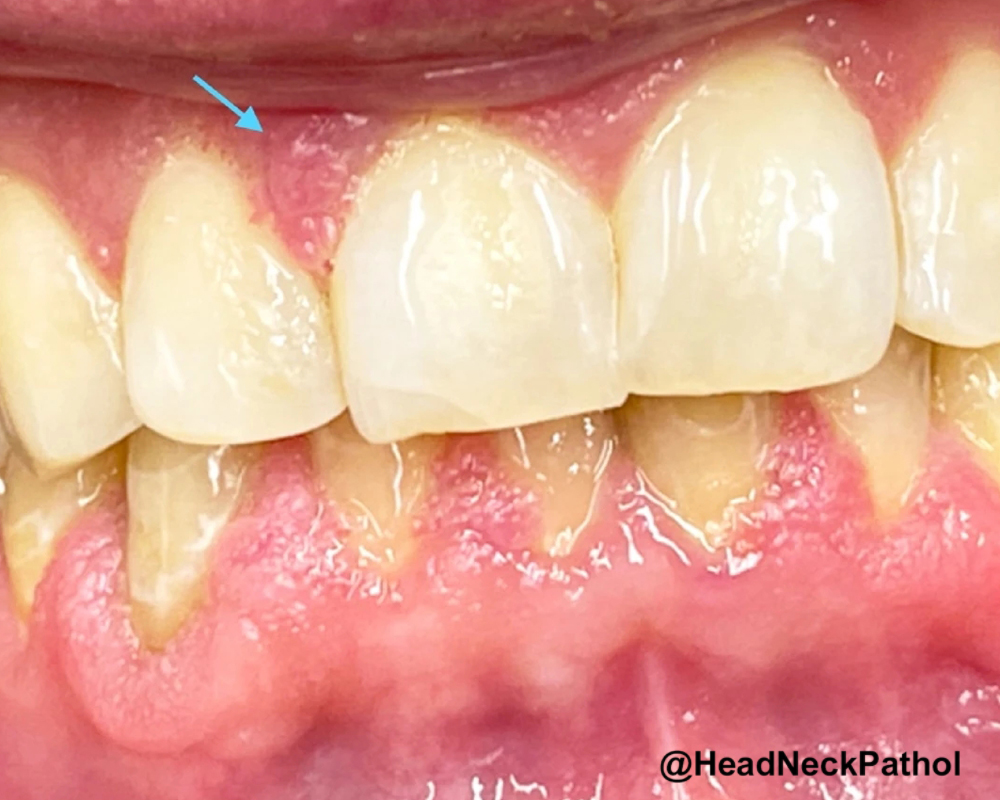

Intraductal Salivary Gland Neoplasms of the Oral Cavity: A Retrospective Case Series with Emphasis on Newly Described Entities